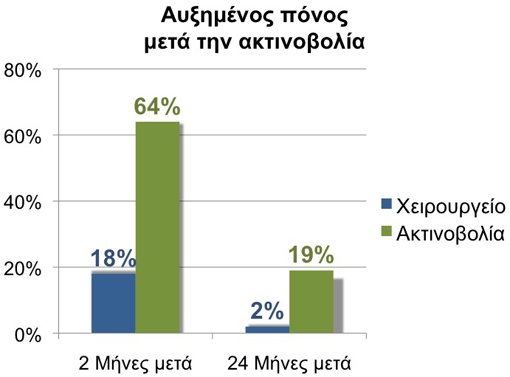

Οι ασθενείς με καρκίνο του προστάτη ανησυχούν επίσης για την εγκράτεια των ούρων και την σεξουαλική λειτουργία μετά την θεραπεία. Όλες οι μέχρι τώρα μεγάλες μελέτες δείχνουν ότι η da Vinci προστατεκτομή παρουσιάζει γρηγορότερη επάνοδο της εγκράτειας των ούρων και χαμηλότερα ποσοστά πόνου σε σύγκριση με τους ασθενείς που υποβλήθηκαν σε ακτινοθεραπεία (βραχυθεραπεία). Διάφορες επίσης μελέτες δείχνουν ότι οι ασθενείς που ήταν προηγουμένως σεξουαλικά ικανοί παρουσιάζουν πλήρη ανάρρωση της σεξουαλικής τους λειτουργίας (οριζόμενη σαν στύση ικανή για κολπική διείσδυση) μέσα σ’ ένα έτος από την da Vinci προστατεκτομη. Η περίοδος ανάρρωσης μπορεί να επιταχυνθεί μέσω ενός ειδικού προγράμματος ανάρρωσης της στυτικής λειτουργίας με την χρήση ασκήσεων και φαρμάκων.

Ασθενείς μετά από ριζική προστατεκτομή αναφέρουν λιγότερους πόνους κατά την ούρηση σε σύγκριση με ασθενείς μετά από ακτινοθεραπεία (βραχυθεραπεία).